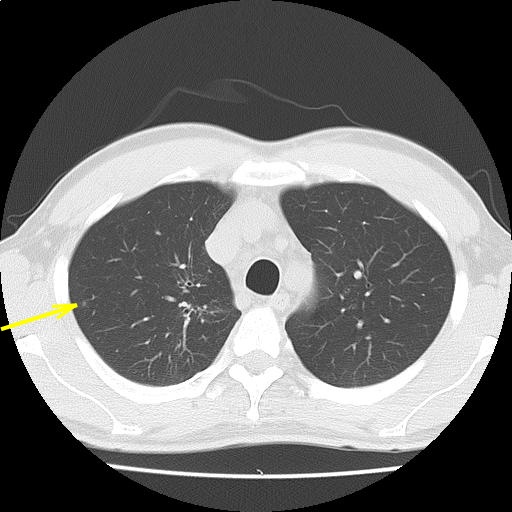

CTスライス画像

(Findings)

両肺末梢に微小結節を散見し、陳旧性炎症性変化と考える。

縦隔リンパ節腫大を認めない。胸水を認めない。